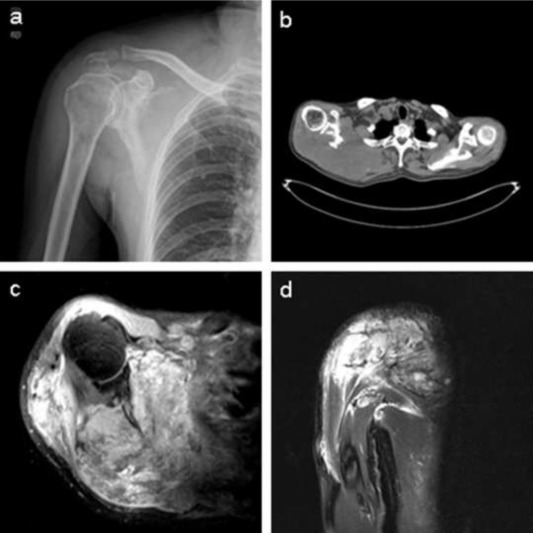

Laboratory tests showed that the serum concentration of CEA reached 17.64 ng/ml. Imaging: X-ray (Fig. 1 a) showed the destruction of the right scapula, and a shadow of soft tissue mass in right scapular region; CT (Fig. 1 b) showed right scapula destructed, surrounded by irregular low-density mass shadow. MRI (Fig. 1 c, d) showed a shadow of soft tissue mass inside of right shoulder, two rounded nodule below the right clavicle, considering as a malignant tumor of the right scapula, right subclavian lymph node metastasis. Emission computed tomography (ECT) showed high metabolism activity in the right scapula, right shoulder and right clavicle bone (Fig. 2 ). Preoperative needle biopsy report: clear cell sarcoma (Fig. 3 ); immunohistochemical staining: PCK (−), LCA (−), Melanoma (−), Syn (+), desmin (−), S-100 (+), CD68 (±), vimentin (+).

Fig. 3.

Histological features. The optical image shows that tumor cells are nested and in shape of polygon or spindle, with nuclear vacuolization and prominent nucleoli (HE × 100).